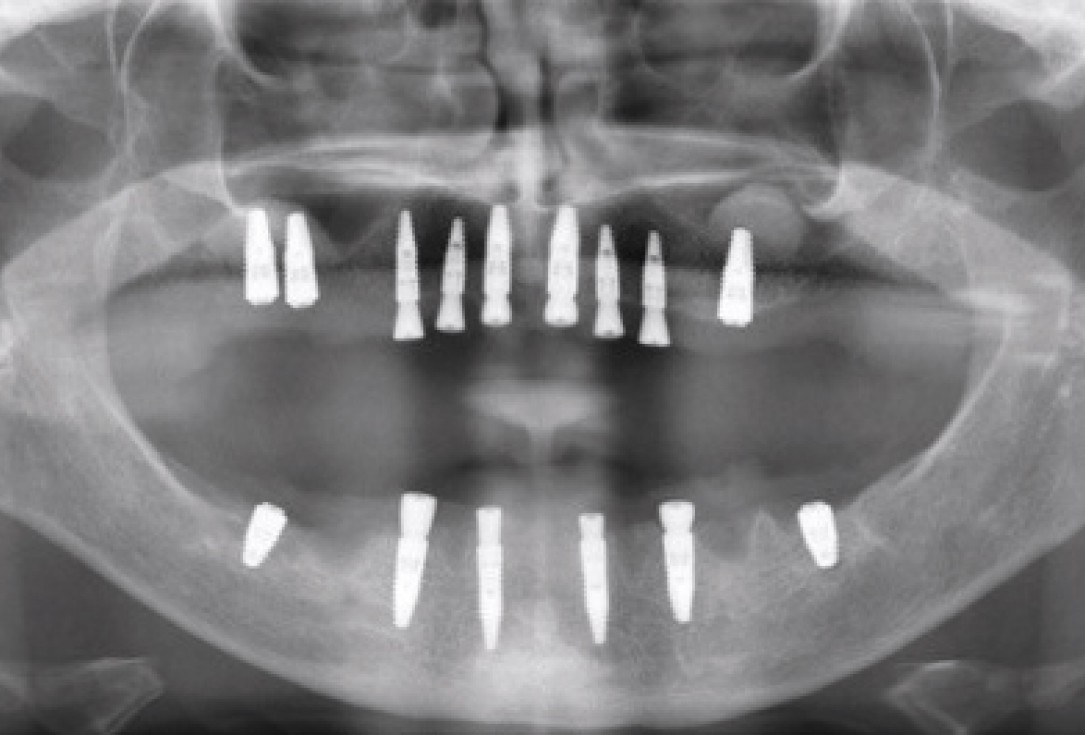

09/11 - Implants placed in the mandible

Sinus lift with maxresorb® inject - Dr. E. Valdimarsson